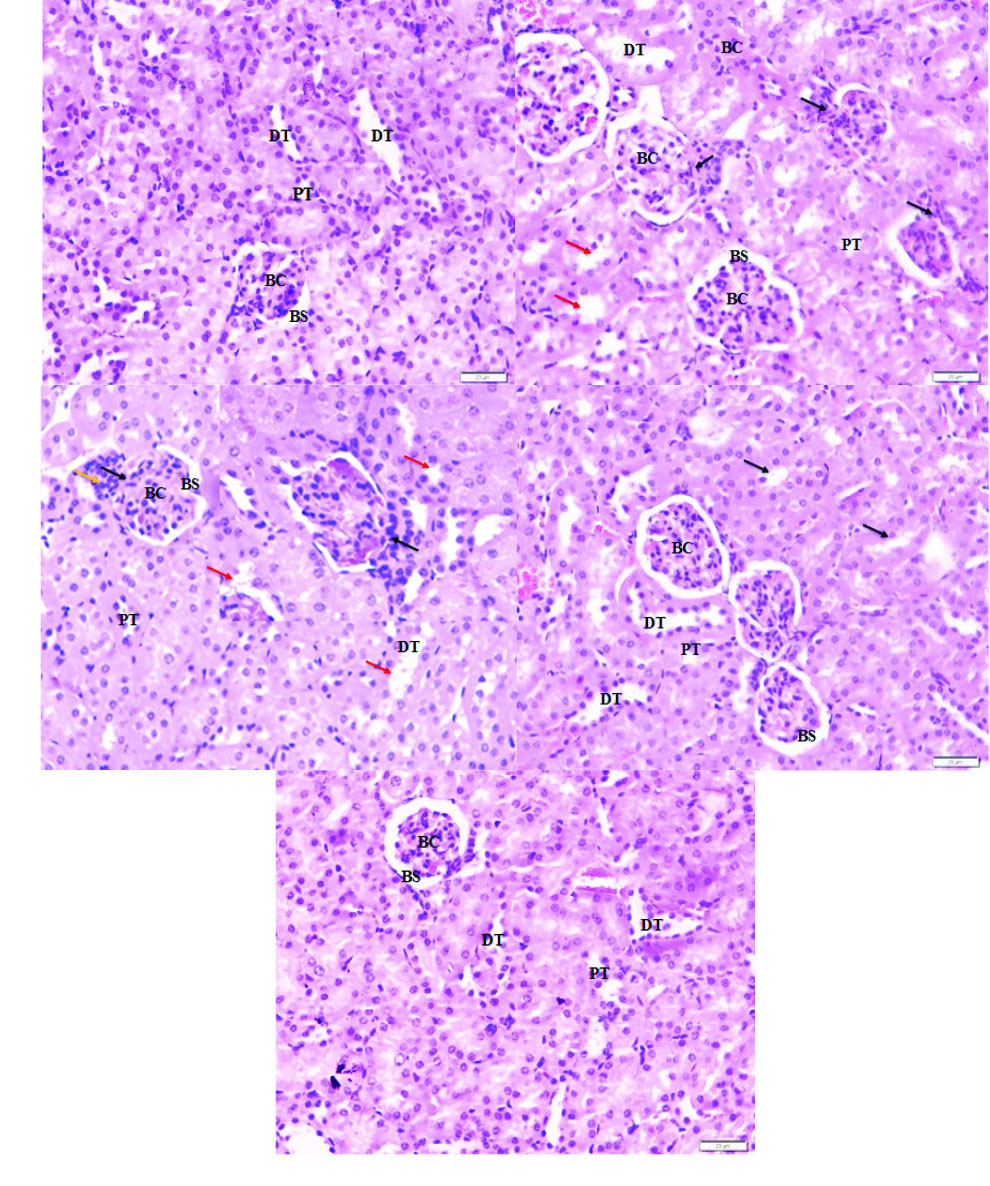

The histological kidney structure of the normal mice, shown in Fig. 3A, exhibited normal Bowman's space surrounding the Bowman's capsule and the renal tubules including proximal tubule and distal tubule. Tissues of EAC tumor group revealed kidney damage including Bowman’s capsule rupture and distortion of the proximal tubule and distal tubule (Fig. 3B). In addition to the changes caused by the tumor, free IFO treatment had caused renal injury due to the presence of lymphocytic infiltration (Fig. 3C). In contrast to the tissues of EAC and IFO groups, the tissues of the mice treated with SAL exhibited moderate damage in Bowman's capsule and renal tubules (Fig. 3D). Interestingly, there were no signs of injury and the structure of the kidney tissue of the SAL-IFO group was ameliorated to be similar to the normal group (Fig. 3E).

Photomicrograph of the histological structure of kidney for the experimental groups of (a) normal group, displaying normal Bowman's space (BS) surrounding the Bowman's capsule (BC), proximal tubule (PT), and distal tubule (DT). (b) EAC group, showing ruptured Bowman’s capsule (black arrow) with distorted feature of proximal tubule and distal tubule (red arrow), (c) IFO group, showing ruptured Bowman’s capsule (black arrow) with lymphocytic infiltration (orange arrow) and injury in proximal tubule and distal tubule (red arrow), (d) SAL group, showing moderate damage in proximal tubule and distal tubule (black arrow) with slight rupture of Bowman's capsule, and (e) SAL-IFO group, showing nearly the same histological structure as the normal group. H&E stain, 400 x magnifications, 20 µm.